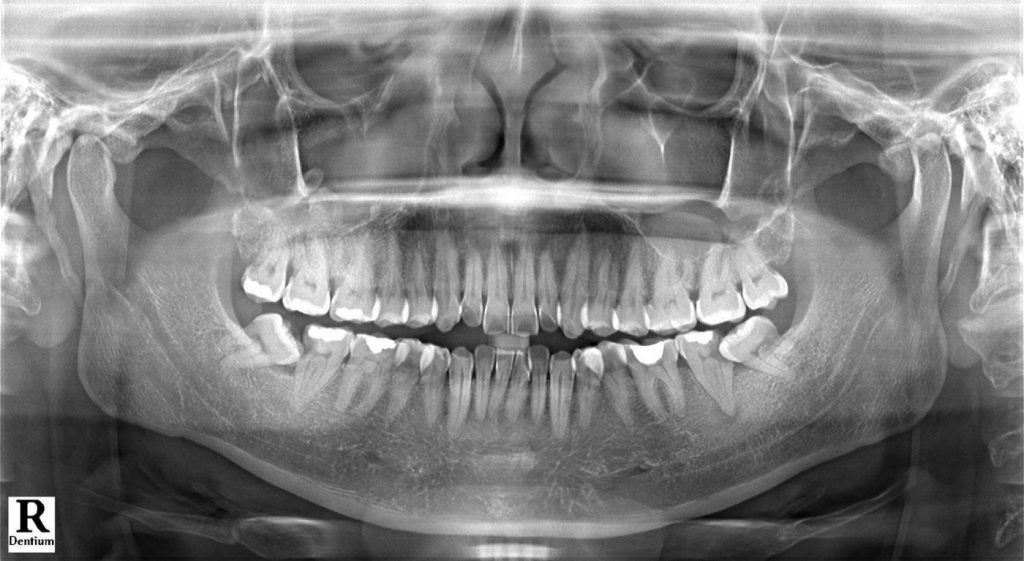

Theo thống kê của hiệp hội nha khoa nha sỹ Hoa Kỳ và các chuyên gia đầu ngành.Trên 90% răng số 8 đều gây ảnh hưởng tới sức khỏe răng miệng